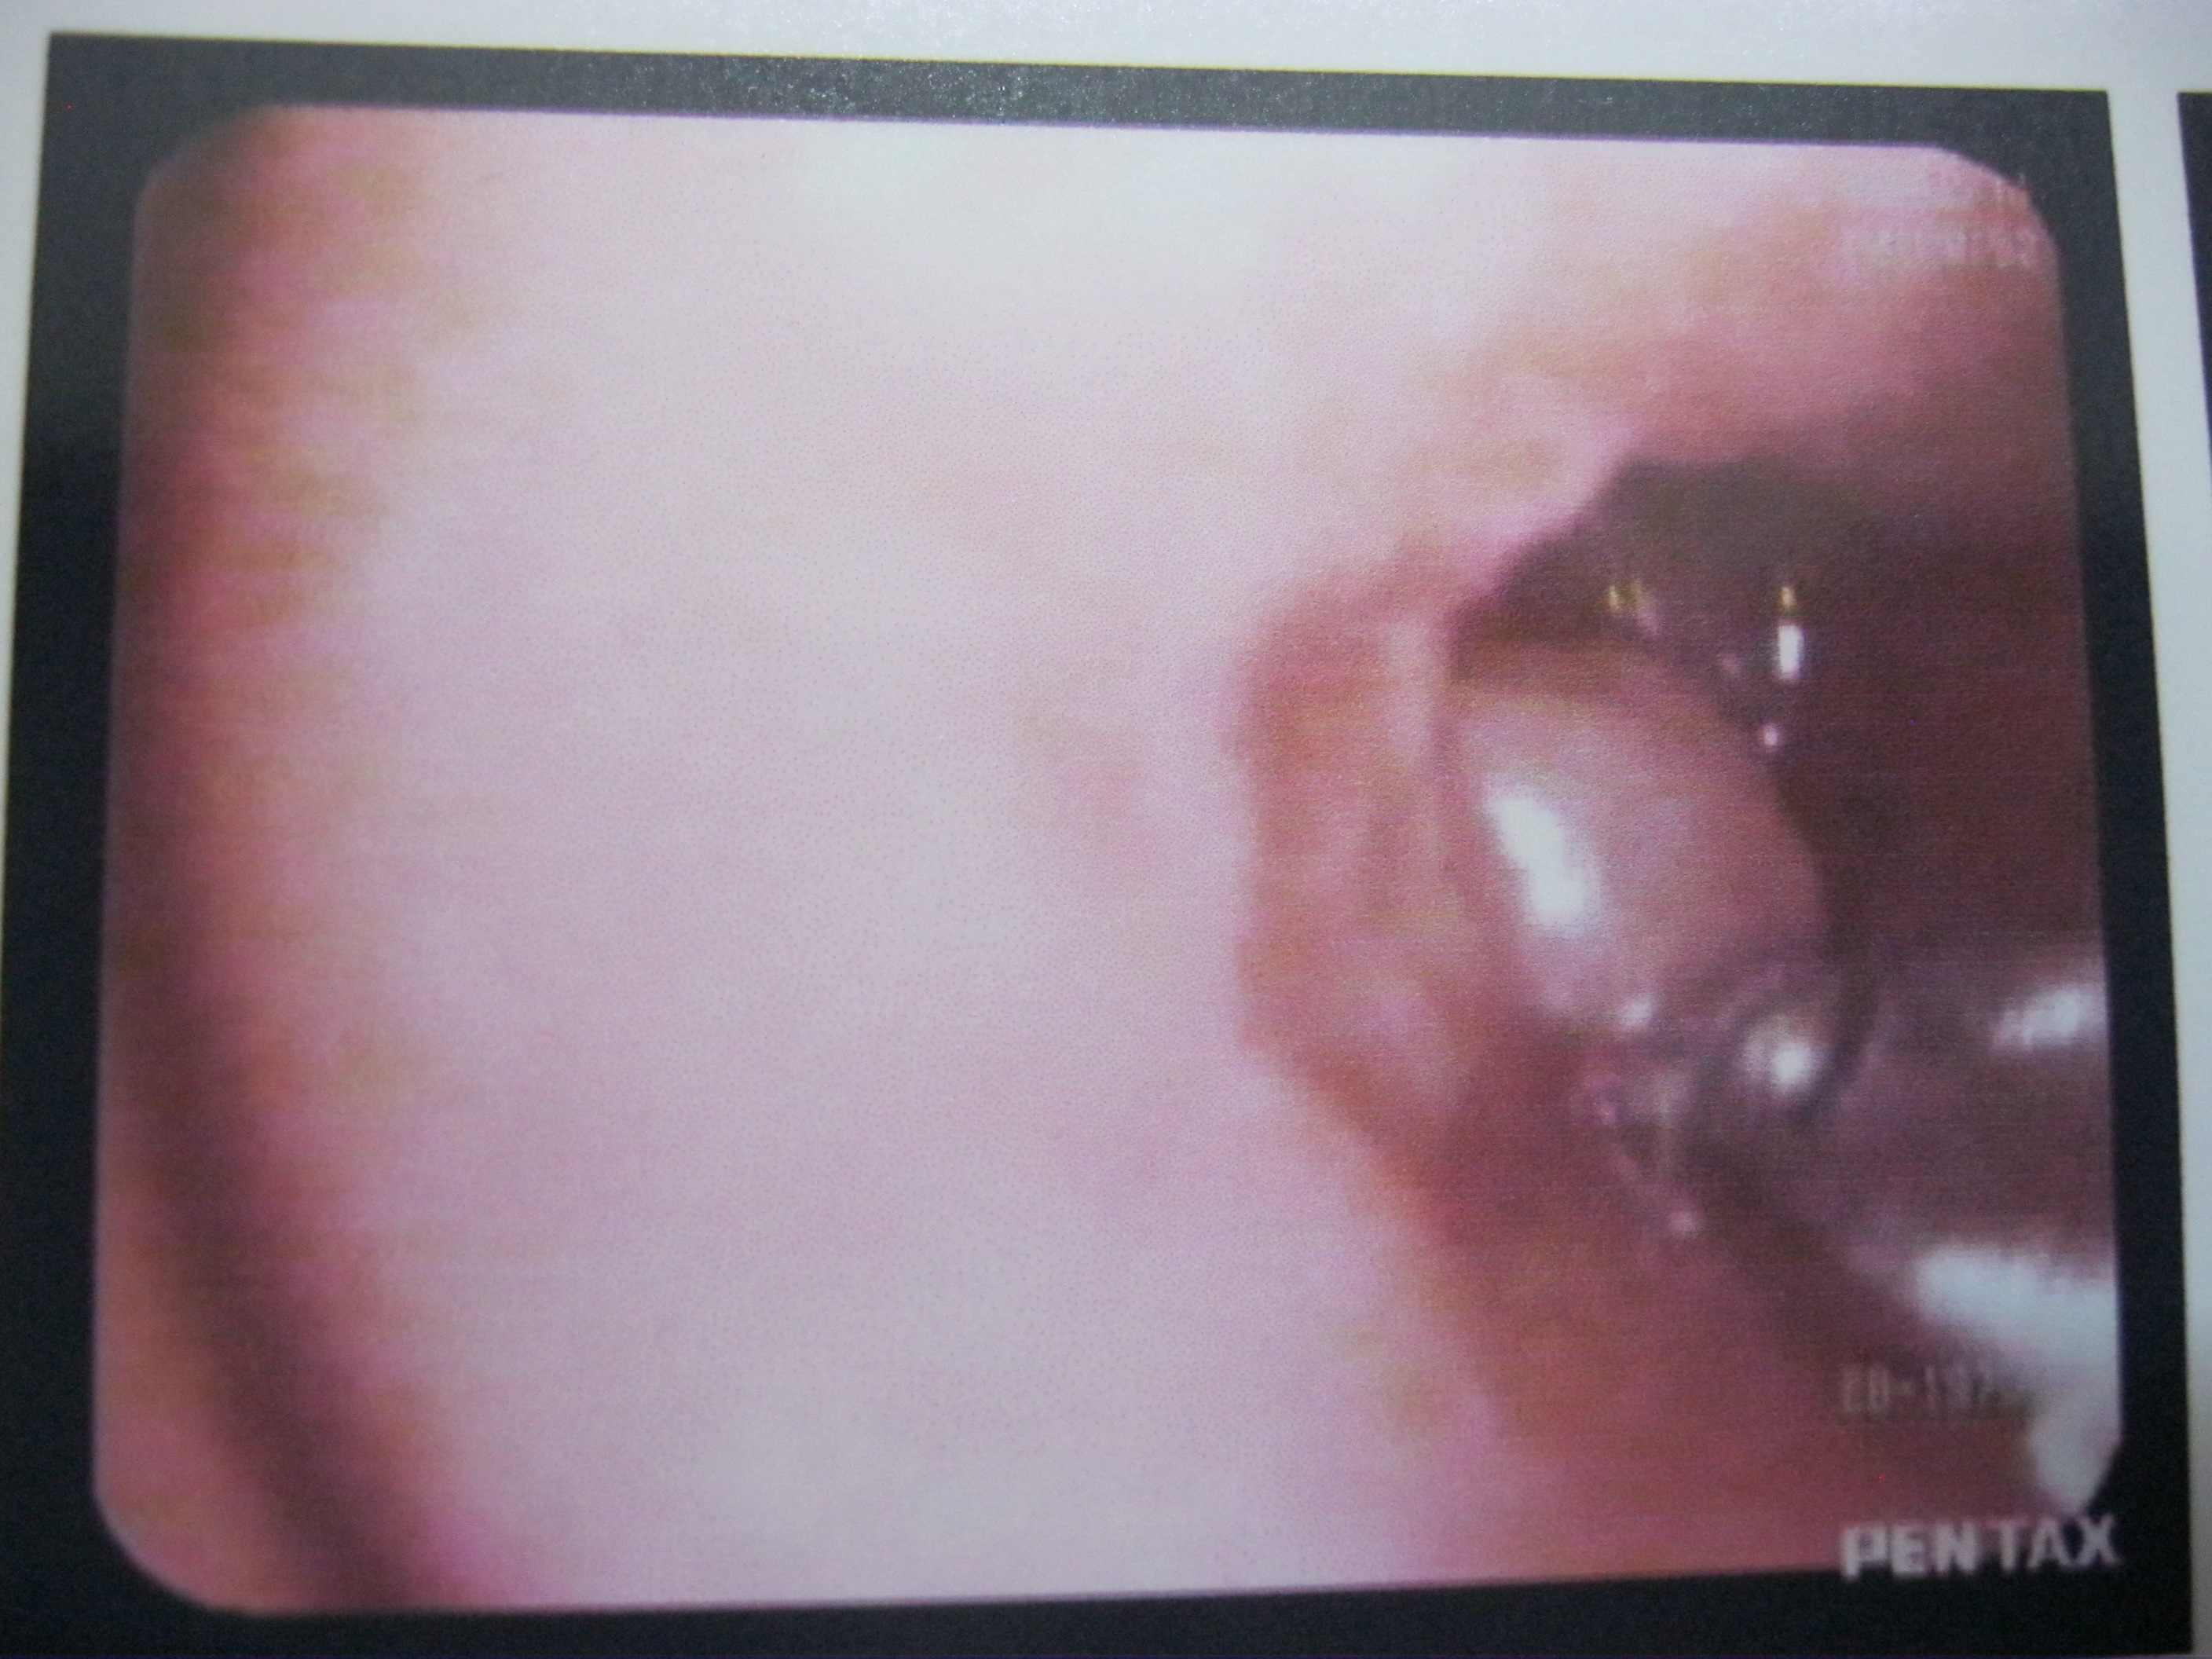

A new state of art for extremely complicated respiratory diseases. Airway interventions means the doctor is visualising areas of lung with a camera attached device(endoscope) so that those diseases which are long standing and not curable by medicines can get good result.

Medical videobronchoscopy

paediatric videobronchoscopy

videothoracoscopy